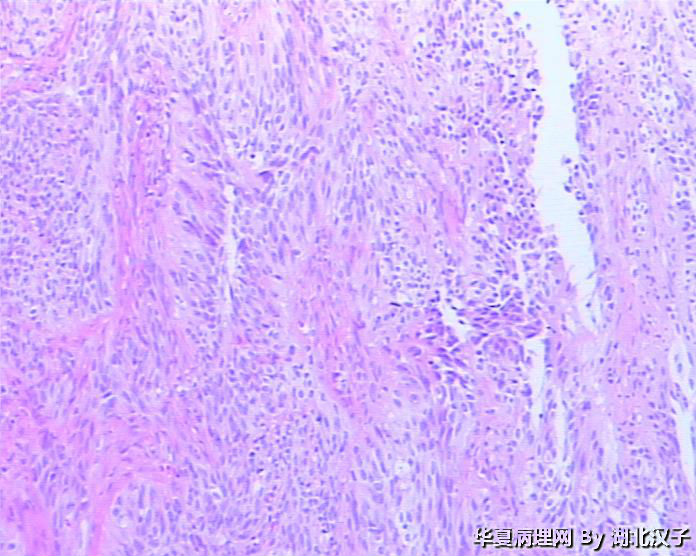

48岁,宫颈肿物

平滑肌瘤??

平滑肌瘤,富于细胞。

平滑肌瘤,富于细胞?

有腺腔样结构,宫颈的上皮状态与图片有相关吗?似巢状浸润。

1、没见到正常宫颈组织;2、没见到肿瘤边缘,如果境界不清则不是平滑肌瘤。